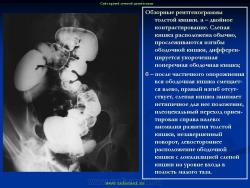

Варианты и аномалии развития толстой кишки.